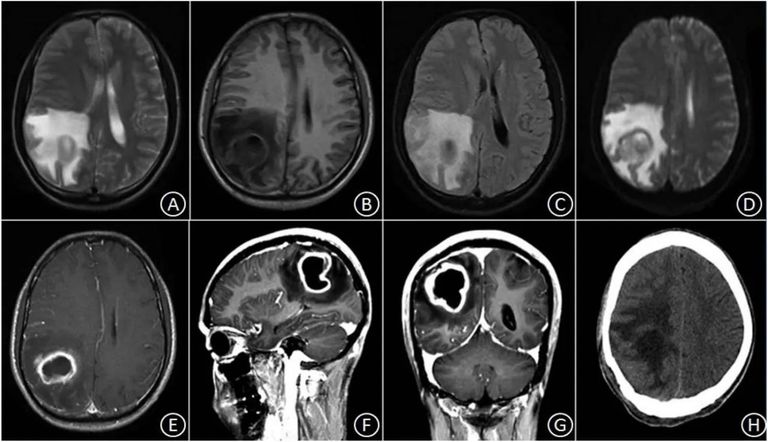

في حادثة فريدة تعود إلى عام 1938 خلال الحرب الأهلية الإسبانية، تعرّض رجل لإصابة مباشرة برصاصة في دماغه ، لكنه نجا بطريقة لا تُصدق. ما حدث بعد ذلك حوّل هذه الإصابة إلى واحدة من أكثر الحالات غرابة في تاريخ الطب العصبي، بعدما استيقظ ليرى ويسمع العالم بشكل مع

بعد تعافيه الأولي، لاحظ المريض أن الأشخاص والأشياء تظهر له من الاتجاه المعاكس لمكانها الحقيقي، كما امتد التشويش ليشمل السمع وأحيانًا حاسة اللمس. كان يرى العالم وكأنه مقلوب ومرآتي في آن واحد، حتى أنه شعر بالارتباك حين رأى عمال بناء يعملون على سقالات تبدو مقلوبة تمامًا أمام عينيه.

لم تتوقف الأعراض عند الانعكاس البصري فقط، بل عانى أيضًا من تشوهات حسية شديدة، مثل رؤية الألوان منفصلة عن الأجسام، وانقسام الأجسام أمامه إلى ثلاث نسخ، إضافة إلى نوبات من عمى الألوان. ورغم غرابة هذه الأعراض، تعامل المريض معها بهدوء لافت.

عالم الأعصاب الإسباني غوستو غونزالو أمضى قرابة نصف قرن في دراسة هذه الحالة الفريدة، ما قاده إلى إعادة التفكير كليًا في كيفية عمل الدماغ. ففي أربعينيات القرن الماضي، اقترح أن الدماغ لا يتكون من أقسام مستقلة، بل من شبكة وظائف موزعة بدرجات مختلفة داخل العضو ذاته، وهو ما كان يناقض النظريات السائدة حينها.